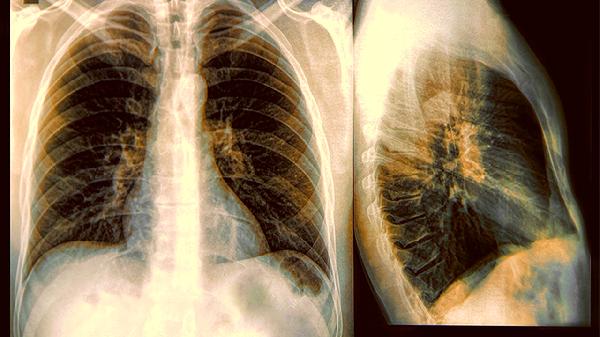

记住,咳嗽不是病,而是身体的警.报系统。当这个警.报出现异常模式时,就是在提醒我们该认真对待了。秋.冬.季呼吸道疾病高发,建议45岁以上人群将低剂量CT纳入年度体检。别让咳嗽成为你忽视的“狼来了”故事,早发现早干预才是关键。